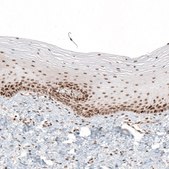

Anti-HLTF antibody is suitable for chromatin immunoprecipitation (ChIP). Anti-HLTF antibody produced in rabbit, a Prestige Antibody, is developed and validated by the Human Protein Atlas (HPA) project . Each antibody is tested by immunohistochemistry against hundreds of normal and disease tissues. These images can be viewed on the Human Protein Atlas (HPA) site by clicking on the Image Gallery link. The antibodies are also tested using immunofluorescence and western blotting. To view these protocols and other useful information about Prestige Antibodies and the HPA, visit sigma.com/prestige.

• IHC tissue array of 44 normal human tissues and 20 of the most common cancer type tissues.